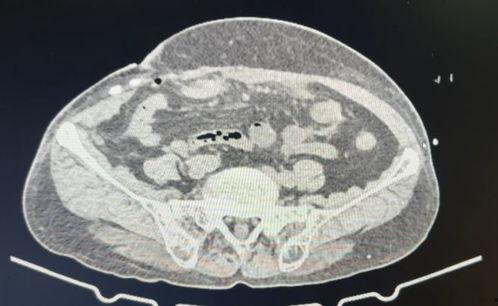

这个视频展示了手术的全过程,包括切开、植入补片、缝合等环节。